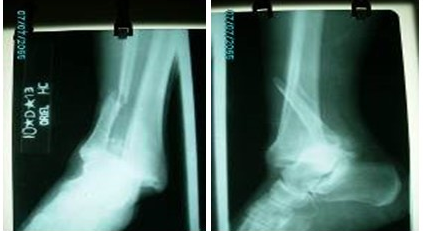

Las imágenes de rayos X mostraron fractura luxación del tobillo derecho. (Fig. 1).

La paciente sufría de una grave fractura- luxación del tobillo derecho con fractura suprasindesmal del peroné, lesión sindesmal, lesión del ligamento deltoideo y fractura del reborde antero externo del pilón tibial.